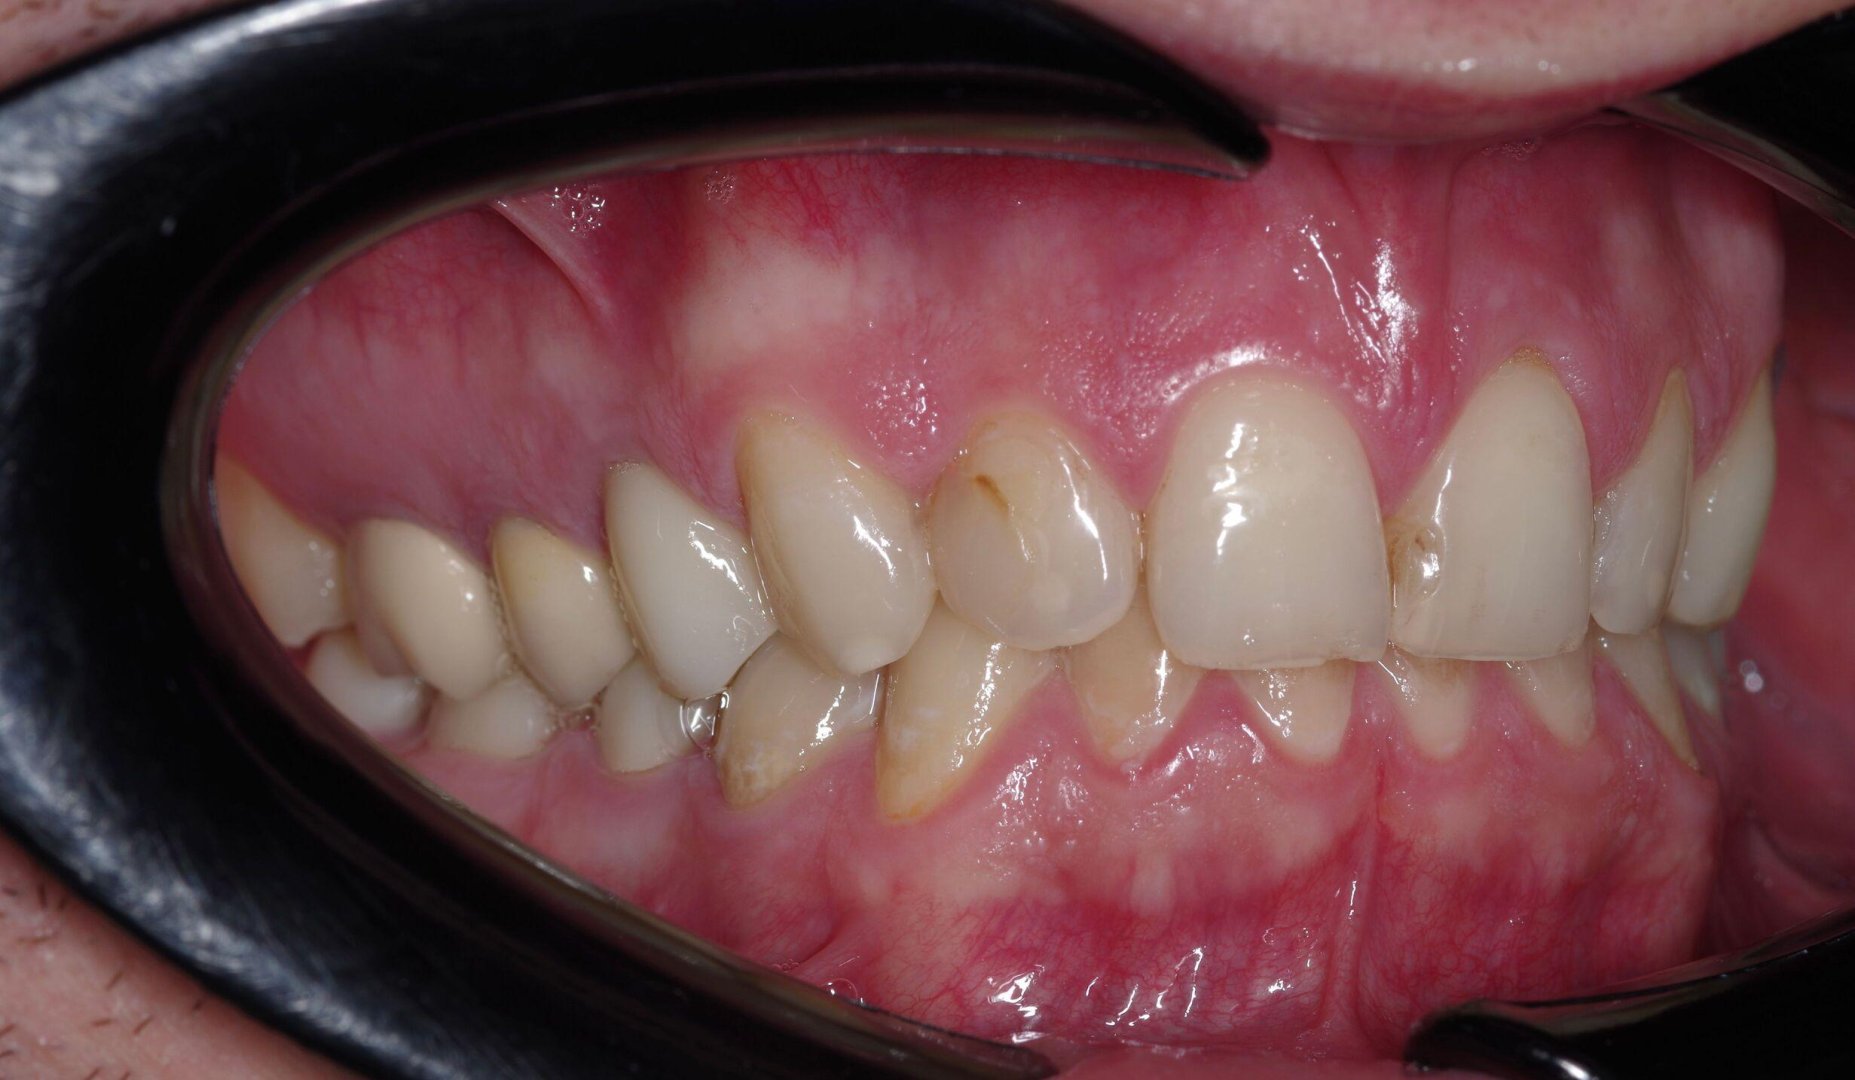

Преображение улыбки: виниры E.max (пример)

Тотальная реставрация зоны улыбки: задача — ровно, светло и при этом естественно. Обратите внимание на «живую» прозрачность и блеск — именно за это E.max любят.

ДО

Виниры E.max — до лечения